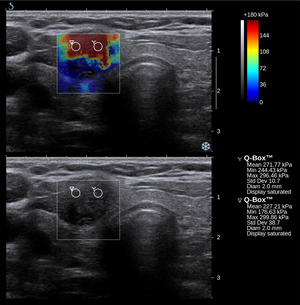

التصوير المرن

Conventional ultrasonography (lower image) and elastography (supersonic shear imaging; upper image) of papillary thyroid carcinoma, a malignant cancer. The cancer (red) is much stiffer than the healthy tissue.